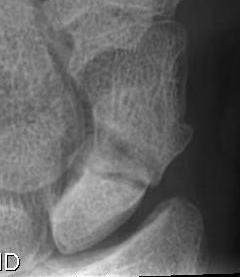

Scaphoid waist fracture 1 mm displaced

Scaphoid fracture with significant displacement

Scaphoid proximal pole fracture